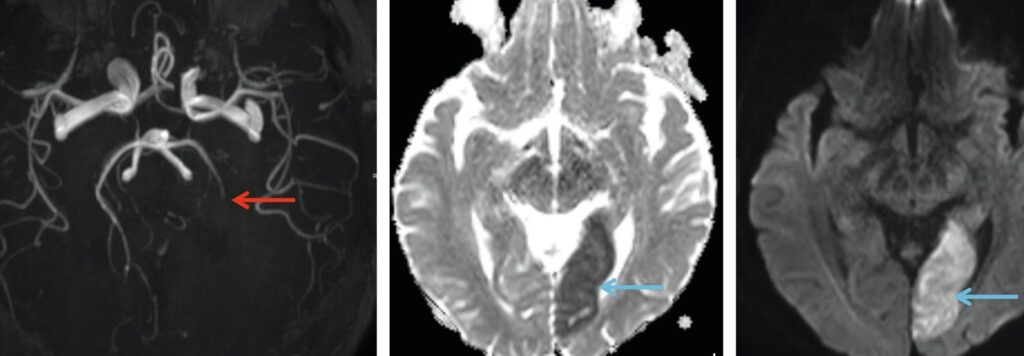

Le scanner cérébral avec injection de produit de contraste représente une avancée significative dans le domaine de l’imagerie médicale. Utilisant des rayons X, cette technique offre une visualisation détaillée des structures internes de l’encéphale, permettant ainsi un diagnostic plus précis de diverses pathologies. L’injection intraveineuse d’un produit de contraste iodé améliore la distinction entre les différents tissus cérébraux et met en évidence d’éventuelles anomalies telles que tumeurs, hémorragies ou malformations vasculaires. Avant de procéder à cet examen, il est important que les patients soient informés des indications et des contre-indications relatives à l’utilisation des produits de contraste. En tant qu’outil diagnostique, le scanner cérébral avec injection demeure un pilier fondamental pour les neurologues, neurochirurgiens et radiologues qui recherchent une compréhension approfondie de l’état cérébral de leurs patients.

Il existe plusieurs types de produits de contraste iodés qui sont couramment utilisés lors des examens de scanner cérébral. Ces agents de contraste sont administrés par voie intraveineuse pour améliorer la qualité des images obtenues et permettre un diagnostic plus précis. Les produits de contraste les plus utilisés incluent l’iodure de sodium, l’iopromide, et l’iohexol. Ils permettent de mieux différencier les tissus mous du cerveau, les vaisseaux sanguins et d’identifier des anomalies telles que des tumeurs ou des hémorragies. Voici leurs caractéristiques principales :